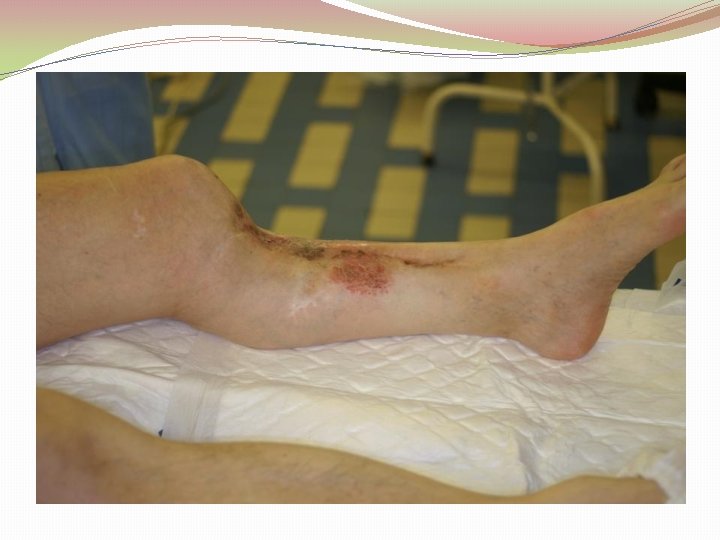

Etioloģija Gustilo-Anderson vaļēju lūzumu klasifikācija I pakāpe brūce mazāka kā 1 cm (punktveida brūce) II pakāpe vaļēja brūce 1 -10 cm III pakāpe IIIA brūce vairāk kā 10 cm, nav mīksto audu defekta IIIB brūce vairāk, kā 10 cm ar mīksto audu bojājumu IIIC Plašs mīksto audu bojājums ar maģistrālo asinsvadu bojājums

Etioloģija Infekciju un amputāciju biežums pēc Gustilo-Anderson klasifikācijas Gustilo pakāpe Infekcijas biežums Amputācijas biežums I 0 -2% - II 2 -7% - IIIA 7% 2, 5% IIIB 10 -50% 5, 6% IIIC 25 -50% Gustilo RB; Merkow RL; Templeman. The management of open fractures. Current Concepts review. J Bone Joint Surg [Am], 72: 299 -304, 1990 Feb